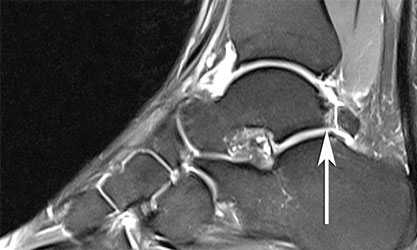

МРТ при импиджмент-синдроме заднего отдела голеностопного сустава

Импинджмент-синдром (impingement syndrome, Neer С.S., 1972) - патологический процесс, развивающийся вследствие стрессовых нагрузок, морфологически обусловленный гипертрофией мягкотканных и/или костных структур, проявляющийся хроническим болевым синдромом и ограничением объема движений в голеностопном суставе.

Соударение, компрессия и микротравматизация уже поврежденных мягкотканных и костных структур вызывает их реактивное воспаление и гипертрофию с формированием фиброзных мягкотканных масс в полости сустава. Фиброзные массы и патологически измененные связки при определенных движениях сдавливаются рядом расположенными костями голеностопного сустава, вызывая болевой синдром. Нередко происходит формирование краевых остеофитов и свободных костно-хрящевых тел в зоне патологических изменений, как результат повторяющейся микротравматизации сочленяющихся суставных поверхностей костей и хронического воспалительного процесса, что приводит к ограничению движений в суставе. Пусковым механизмом в развитии этого синдрома является хроническая перегрузка или травма голеностопного сустава. В ряде случаев причиной развития импинджмент-синдрома голеностопного сустава является повреждение дополнительных связок или сверхкомплектных костей.

МРТ для диагностики недуга не является обязательным исследованием. Его выполнение рекомендуется, если необходимо провести дифференциальную диагностику с другими патологиями либо в начальных стадиях патологии.